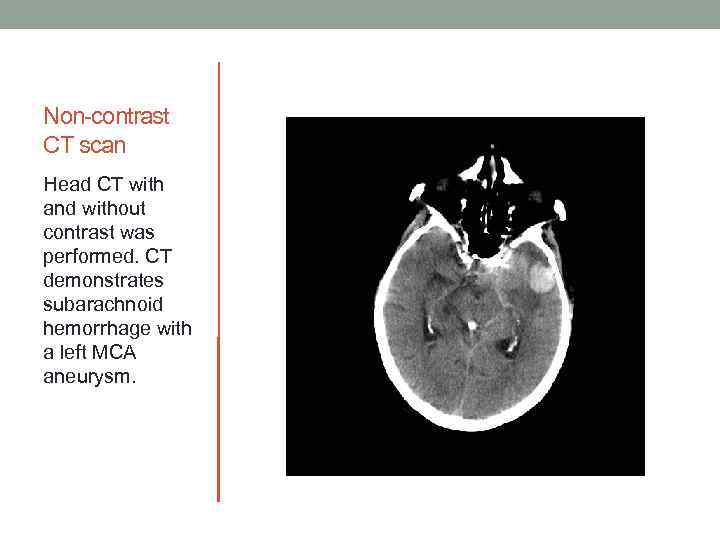

Non-contrast CT scan Head CT with and without contrast was performed. CT demonstrates subarachnoid hemorrhage with a left MCA aneurysm.